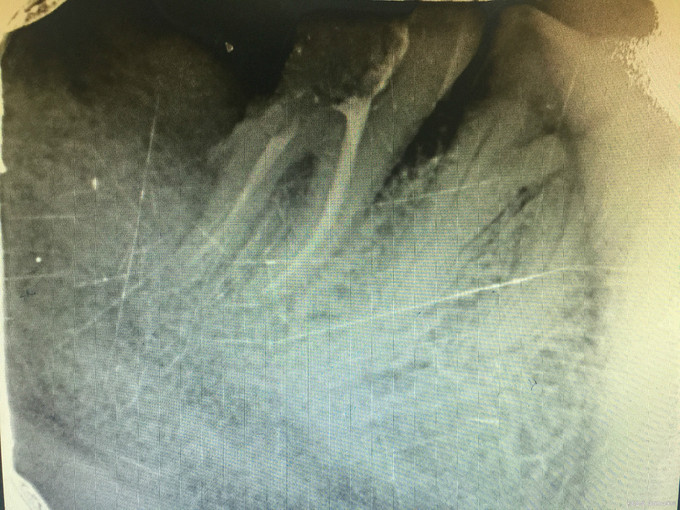

临床检查:47远中龋坏,探疼(+),冷(++),叩(-),松动度(-),牙周正常. 48未完全萌出, 辅助检查:X线示47远中龋坏累积髓腔,48近中水平阻生。

诊断:47牙髓炎,48阻生齿 治疗:经患者知情同意后,48拔除,47局麻去腐降牙合,开髓拔髓寻找根管口,建立直线通路,扩通根管,确定工作长度。S3/EDTA凝胶镍钛器械,低浓度次氯酸钠冲洗根管,预备至35/04,氢氧化钙诊间封药,一周后复诊,试主尖X线示恰充,试干根管,导AH-PLUS糊剂,VDW热压胶垂直加压根充,术后见根管恰充,暂封调合抛光。观察桩冠修复。